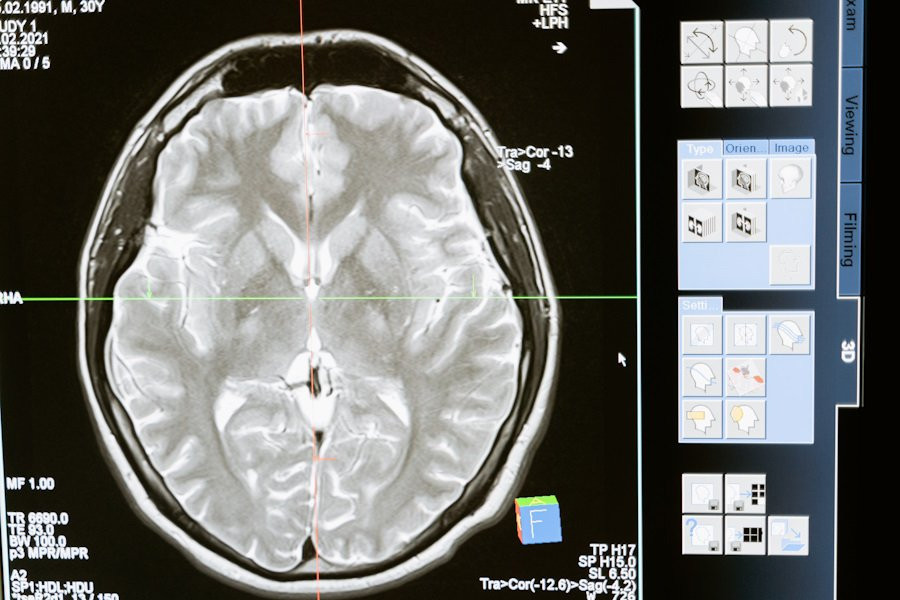

Ученые анализировали показатели исследования, охватывающего 3 поколения (начиная с 1948 г), чтобы оценить влияние степени содержания кортизола на когнитивные функции (память, логика и внимание) и на объем мозга, сосредоточив внимание на белом веществе, отвечающем за передачу нервных импульсов.

Особенно у женщин с высоким уровнем кортизола наблюдалось уменьшение объема мозга. Ученые также обнаружили признаки повреждения белого вещества у участников с повышенным уровнем кортизола, что, по их мнению, может быть связано с отличиями в памяти и внимании по сравнению с другими группами.